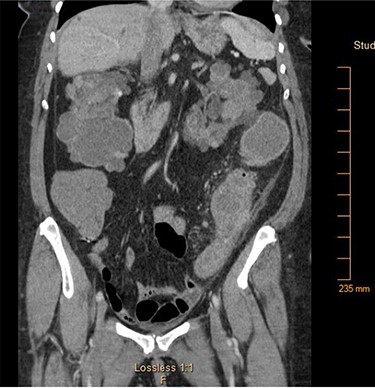

A 65-year-old African American female with history of end-stage renal disease secondary to autosomal dominant polycystic kidney disease presented our Emergency Department with abdominal pain and hematochezia. She was evaluated with esophagogastroduodenoscopy and colonoscopy, which showed multiple non-bleeding sigmoid diverticula and descending colon mucosal erosions consistent with colitis. She was treated medically with metronidazole and ciprofloxacin. Her symptoms recurred 1-week after hospital discharge. She complained of intermittent, severe left lower quadrant pain with associated nausea and non-bilious emesis. Computed tomography (CT) on re-admission showed thickening of the descending-sigmoid colon junction with fluid-filled, dilated colon proximally (Fig. 1). Given symptoms and CT imaging consistent with early large bowel obstruction, the patient was taken to the operating room for exploratory laparotomy, sigmoid colectomy and end colostomy. Surgical pathology revealed pericolonic abscess and Sevelamer crystals (Fig. 2). The patient’s Sevelamer was discontinued, and her postoperative course was uncomplicated. She was seen back for planned elective colostomy reversal 4 months after her initial operation.

Computed tomography of the abdomen and pelvis showing focal narrowing of the sigmoid colon with proximal colonic dilatation.